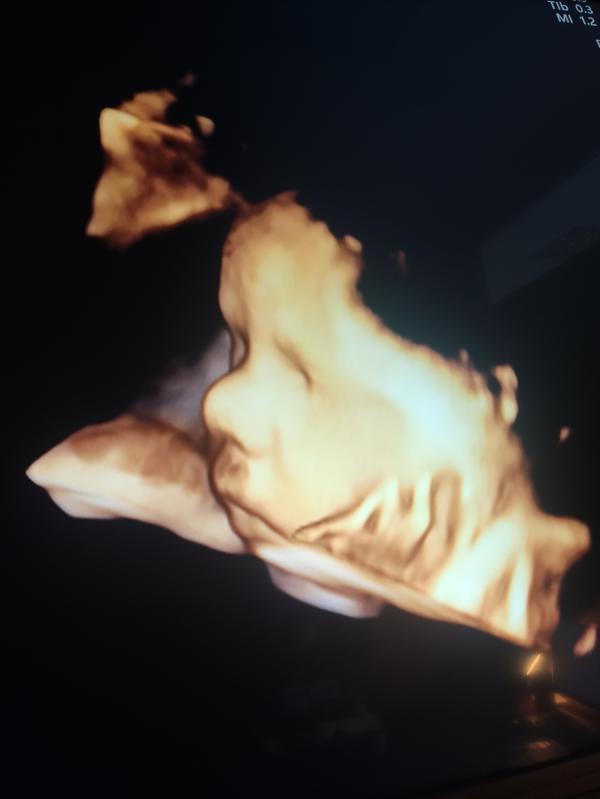

32 неделя♥️ отеков нет, самочувствие вроде нормальное ,но есть одно но... Гемоглобин не повышается. Малыш в течении дня шевелится потихоньку ,а перед сном у нас начинаются гонки по вертикали. На узи ставят крупный плод ,мы весим уже 2,1кг.

Еще у нас обвитие пуповиной 😔 осень переживаю за малыша... Девочки у кого так было?